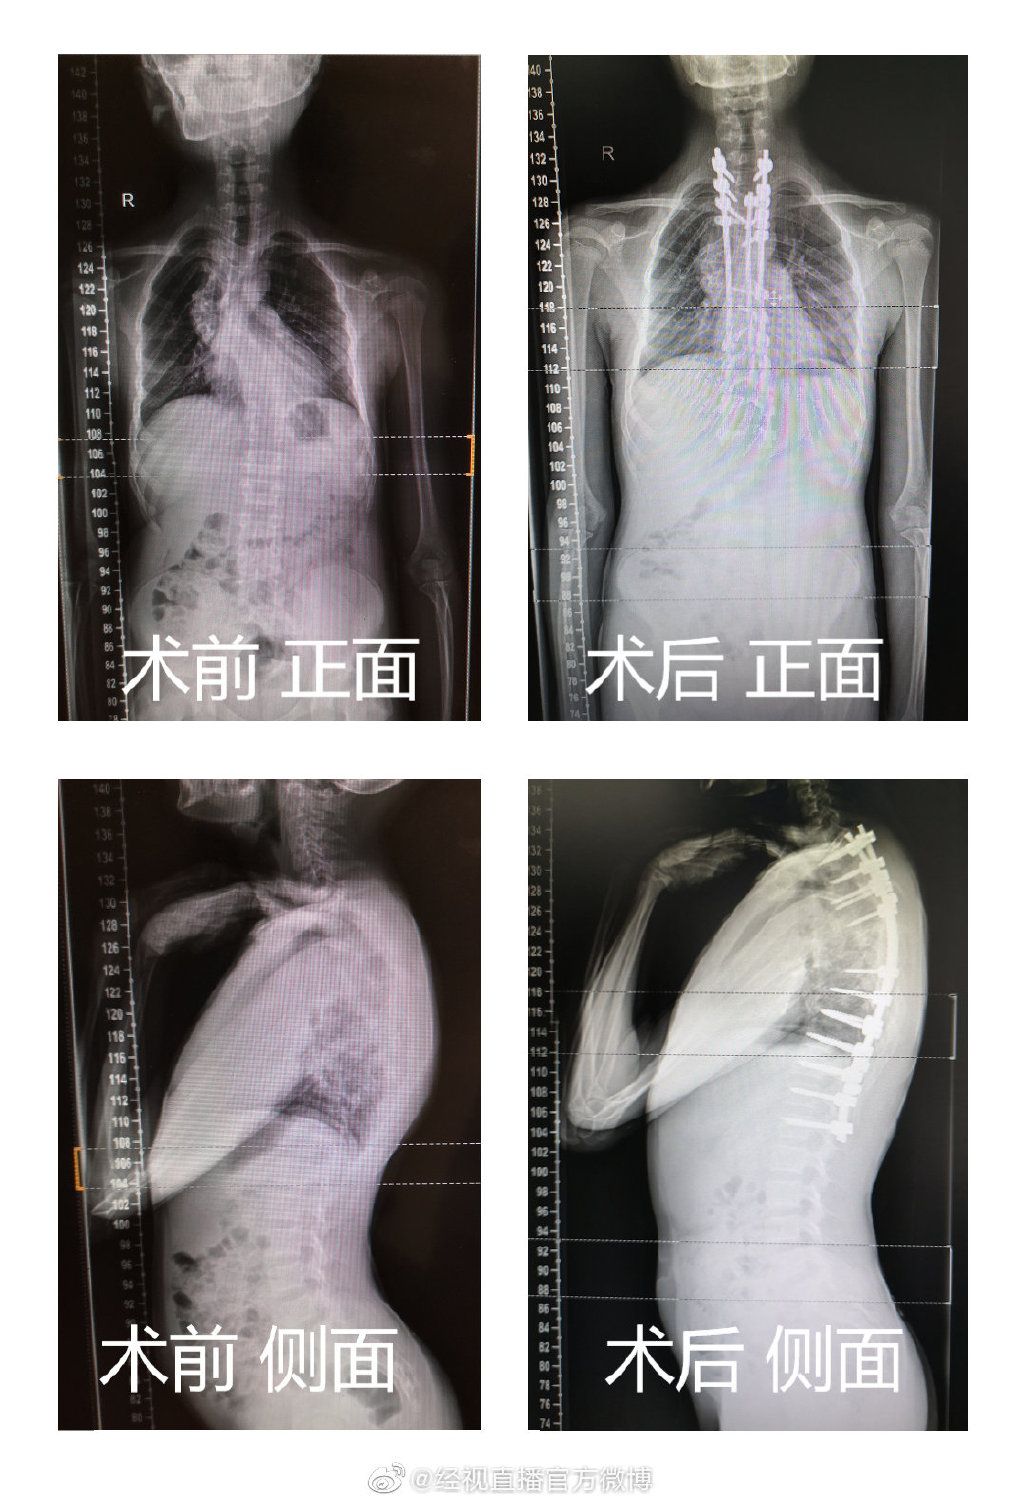

10岁的湖北男童涛涛,两年前被确诊为神经纤维瘤合并脊柱侧弯,起初孩子身体没什么影响,可慢慢进入青春期后,孩子身体涨势迅猛,脊柱侧弯的度数却在快速增加,从原本的40度发展成89度。严重扭曲的脊柱占据了原本属于心肺和消化道的空间,涛涛的心肺、消化系统都受到严重压迫,孩子的背也越来越驼,更是出现呼吸困难、吃不下东西的症状。辗转多院后,在武汉儿童医院,医生耗时7个半小时做手术,成功用20根钢钉扶正孩子扭曲的脊柱,脊柱侧弯度数从89度缩减至15度。

10岁的湖北男童涛涛,两年前被确诊为神经纤维瘤合并脊柱侧弯,起初孩子身体没什么影响,可慢慢进入青春期后,孩子身体涨势迅猛,脊柱侧弯的度数却在快速增加,从原本的40度发展成89度。严重扭曲的脊柱占据了原本属于心肺和消化道的空间,涛涛的心肺、消化系统都受到严重压迫,孩子的背也越来越驼,更是出现呼吸困难、吃不下东西的症状。辗转多院后,在武汉儿童医院,医生耗时7个半小时做手术,成功用20根钢钉扶正孩子扭曲的脊柱,脊柱侧弯度数从89度缩减至15度。